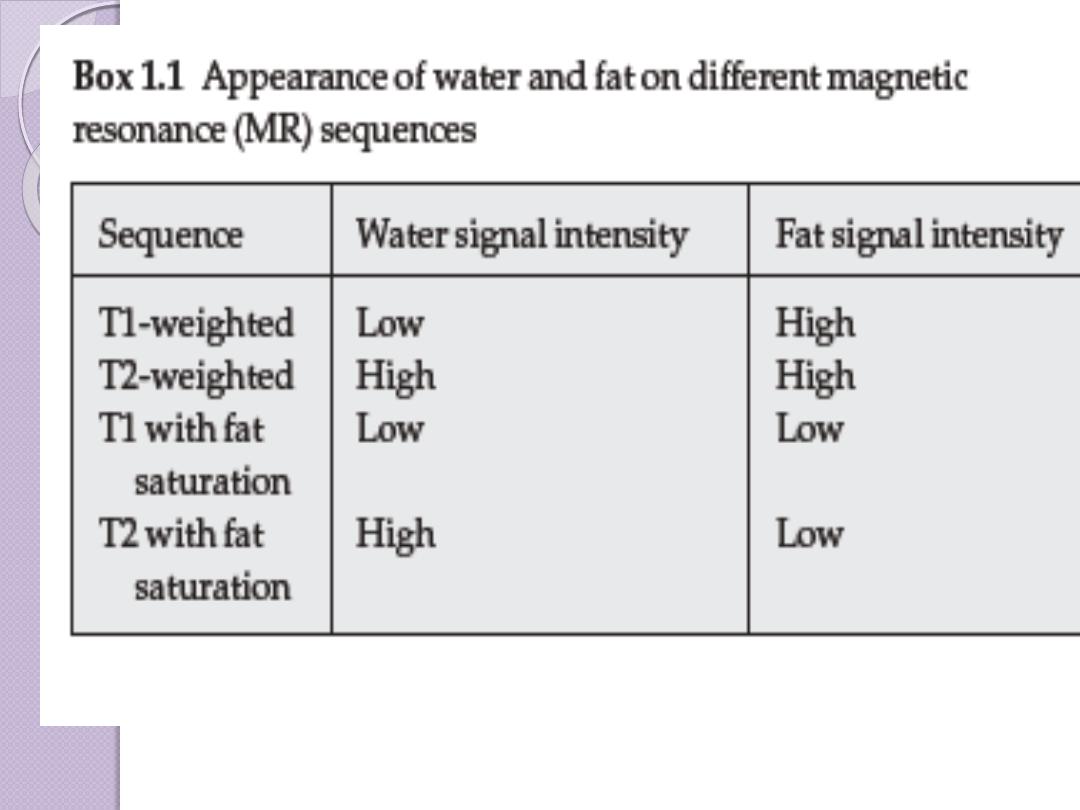

The appearance of

an MR image is a

function of the

chemical

composition of the

various types of

tissue

bone

fat

muscle